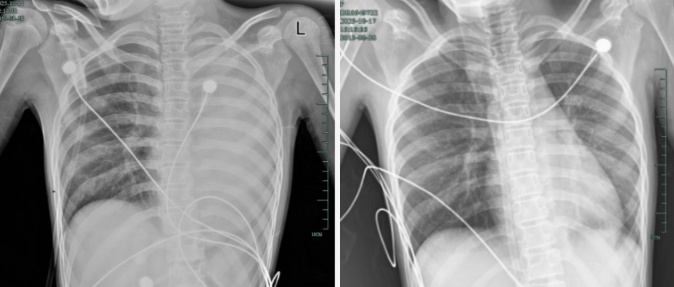

入院后,玲玲很快出现呼吸急促、胸闷胸痛症状,体温38.5℃,只能靠 5L/min 的面罩吸氧维持血氧,胸片显示左肺已完全呈 “白肺” 改变,肺部炎症进展迅猛。

治疗前,左肺呈“白肺”状态;治疗后,“白肺”被吸收,心脏边缘清晰可见